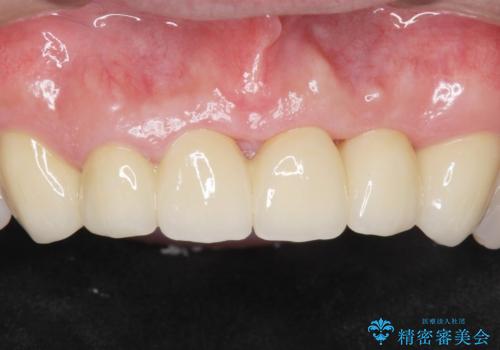

自然な仕上がりと咬み心地に大変ご満足頂けました。

「以前は出っ歯だったのにブリッジにしたことで歯並びもきれいになった!」と喜んで下さいました。

クラウンの種類:オールセラミッククラウン スタンダード